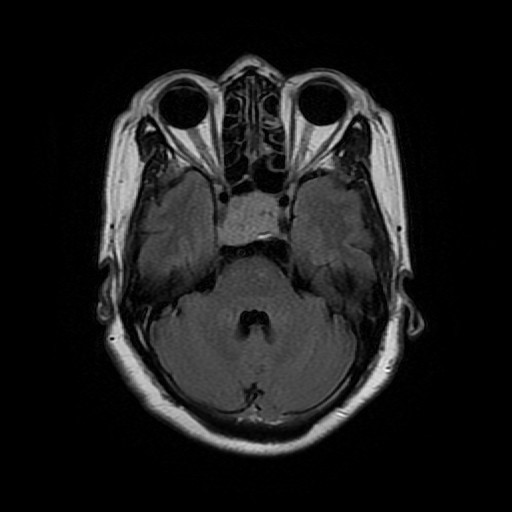

查体:双眼各向视野检查不合作,双侧眼球各向运动灵活,无复视,双侧瞳孔等大等圆,对光反射灵敏,双侧鼻唇沟对称,伸舌偏右,左侧巴氏征可疑阳性。 辅助检查:外院头颅MRA平扫+增强:鞍区巨大含多发囊变肿块(大小约5.6cm*3.8cm*6.6cm),血供稍丰富并包绕左侧大脑前动脉A1段,两侧颈内动脉海绵窦段受压,左侧脑室前角可疑侵犯,性质待定(颅咽管瘤?垂体瘤?其他?);双侧脑室重度扩张积水;双大脑半球部分脑沟信号增高,渗出?少许蛛网膜下腔出血?

诊断:鞍区肿物(性质待查?) 治疗:入院后行头颅MR平扫+增强+MRA示::1、鞍区、鞍上占位,考虑垂体大腺瘤囊变、卒中,突向第三脑室生长,第三脑室、右侧侧脑室扩张,左侧侧脑室受压变窄、移位。2、MRA示脑动脉硬化,右侧颈内动脉、大脑前动脉A1、2段受压移位。遂排除手术禁忌症,于全麻下行“神经内镜辅助下经额鞍区鞍上及脑室内巨大肿物切除术+脑室外引流术”,术后病理示:术后病理示:(鞍区、鞍上及脑室内占位)肿瘤由圆形细胞构成,细胞形态较一致,部分细胞胞浆红染,部分透亮,部分细胞有异型性,核分裂象少见,结合免疫组化及临床,符合垂体腺瘤。 免疫组化结果(②):ACTH(-),PRL(-),TSH(-),FSH(+),GH(-),LH(-),Ki-67(1%~2%+),GFAP(-),CD56(+),CgA(+),Syn(+)。